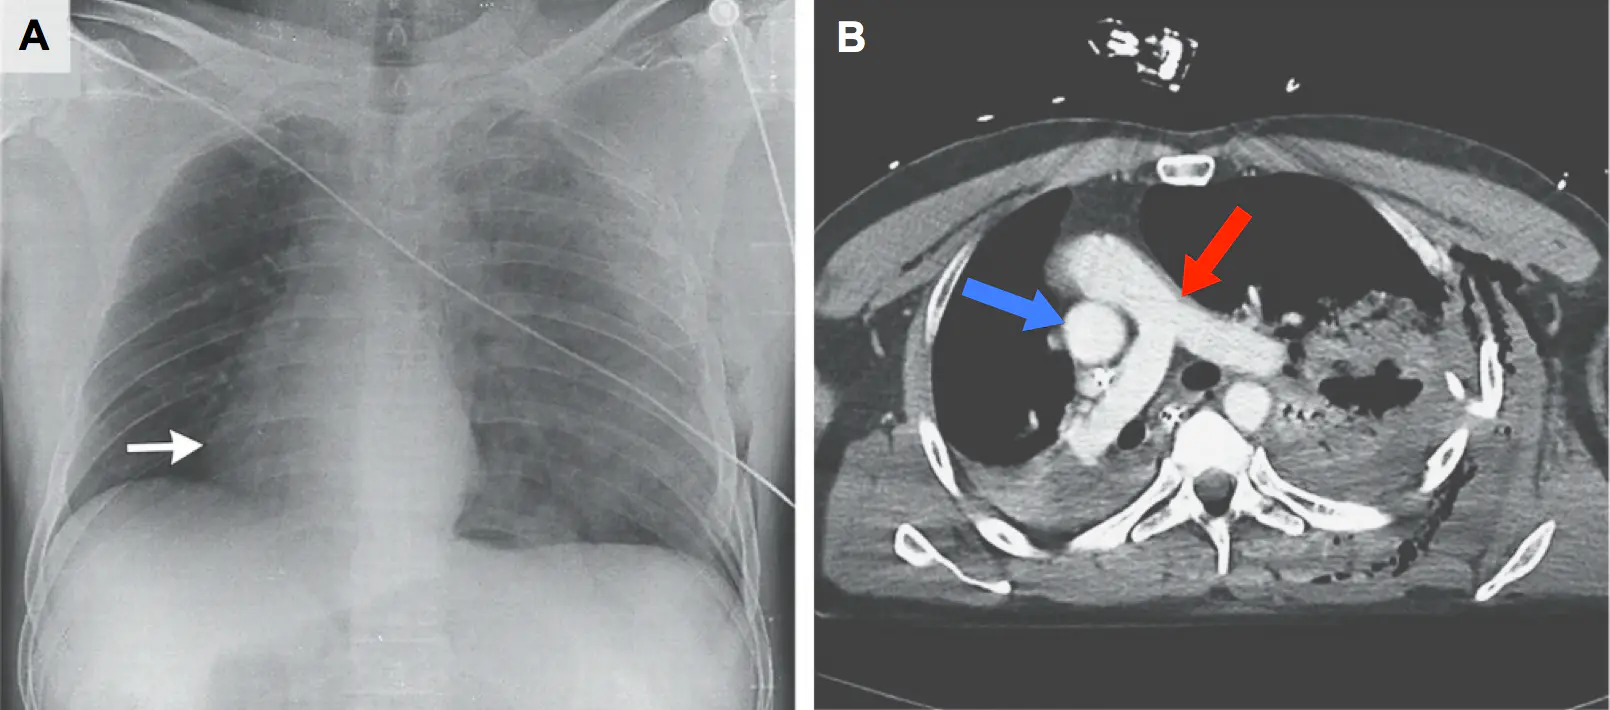

Les radios et les scanners ont démontré qu'il n'en était rien : le cœur ne s'était pas développé à droite, mais avait récemment basculé de 90° dans sa cage thoracique (cliché A). L'artère aorte (flèche bleue) et l'artère pulmonaire (flèche rouge) sont, sur le scanner (cliché B, vu du dessous), très clairement mal positionnées. La section de l'aorte (qui apparaît comme un rond blanc) et la partie avant de l'artère pulmonaire (la partie arrondie que l'on voit au-dessus de l'aorte) devraient être côte à côte, et placées parallèlement à l'avant de la cage thoracique.

Ce déplacement du cœur était la conséquence d'un pneumothorax (épanchement d'air dans la plèvre), qui a fortement comprimé les poumons, entraînant la formation un espace dans lequel le cœur a pu se mouvoir. Les artères du patient étaient suffisamment souples pour ne pas former de coude, ce qui aurait eu pour effet de bloquer la circulation sanguine et d'entraîner sa mort.

Un peu plus de 24 heures après que l'air ait été drainé hors de cet espace pleural, le cœur du patient s'est repositionné à gauche, de façon naturelle (clichés C et D).